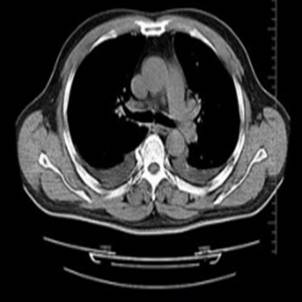

CT发展共经历了五代,1、2、4、5代CT逐步北市场淘汰,螺旋CT是在第3代CT的基础上发展起来的。

5min(了解):CT的发展分代、扫描方式及特点。 3min 思政元素:上海联影医疗科技有限公司作为国内医疗设备著名企业,肩负振兴民族工业的历史重任。国内医疗器械行业水平与国外同行差距大,追赶路的崎岖而漫长,需要几代人的不懈努力,当下青年正当时。 8min(掌握):讲解CT设备各方面的发展方向